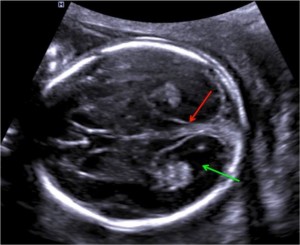

این تصویر مقطعی از سر جنین در سطح بطن مغزی جانبی در طول آزمایش در هفته 21 بارداری را نشان میدهد. اندازه گیری BPD (قطر دو طرفه)، HC (دور سر) و VP (شاخ خلفی بطن جانبی) باید دقیقا در این دیدگاه مغز جنین انجام شود. آناتومی مغز جنین نیز باید بررسی شود. فلش قرمز به خط اکوژنیک CNS متصل است که به طور معمول مغز را به دو نیمکره تقسیم می کند. فلش سبز به قسمت خلفی بطن جانبی اشاره می کند، که باید اندازه گیری شود (اندازه طبیعی کمتر از 10 میلی متر است).